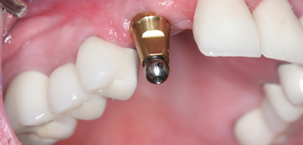

Implant